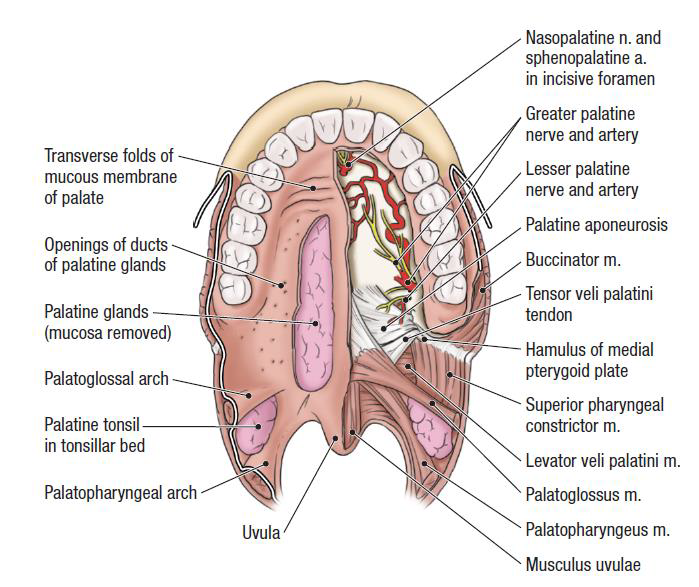

上顎

- Greater palatine foramen

- Lesser palatine foramen

- Greater/ lesser palatine n.

- Palatine process

- Incisive canal

- nasopalatine n. and vessel